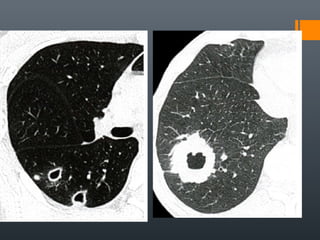

O documento discute vários conceitos radiológicos incluindo consolidação, atelectasia, nódulos, pseudocavidades e padrões intersticiais, fornecendo definições, sinais e diagnósticos diferenciais para cada tópico. Ele também discute a redução da atenuação pulmonar e fornece um link para mais informações.